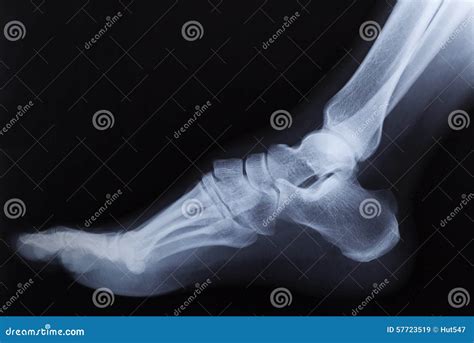

When you visit an urgent care clinic or an emergency room with ankle pain, the physician will first perform a physical examination. However, even the most experienced doctor cannot confirm a fracture just by looking at the surface. A broken ankle Xray is necessary to visualize the internal structure of the joint. It provides a clear, two-dimensional image of the tibia, fibula, and talus, allowing medical professionals to rule out or confirm a break.

• Positioning: You will be asked to sit or lie down on an examination table. The technician will position your ankle in three standard views: an anterior-posterior (front), lateral (side), and a mortise view (a slightly rotated view that better visualizes the joint space).